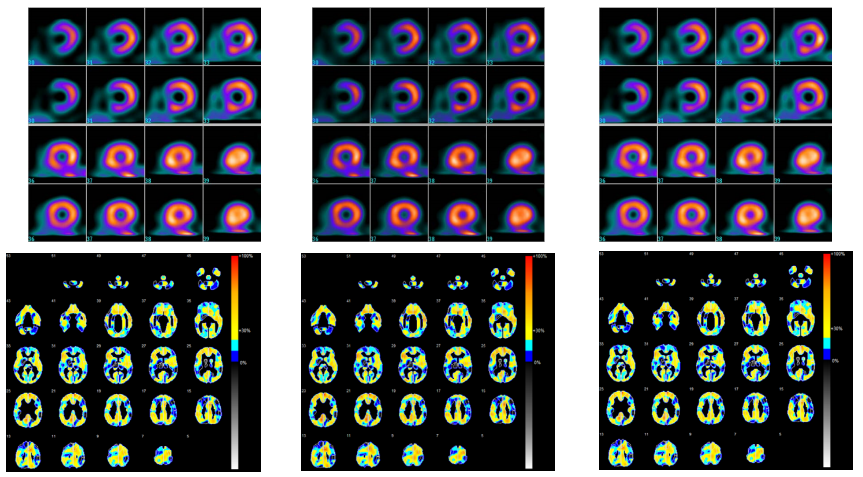

Poniżej zestawiono oceniane obrazy dla porównania.

Rys. 12 Przykładowe obrazy RI (Hybrid Gamma PXL, po lewej, GSDF w środku, 2.2 po prawej)

Rys. 13 Przykładowe obrazy ES (Hybrid Gamma PXL po lewej, GSDF w środku, 2.2 po prawej)